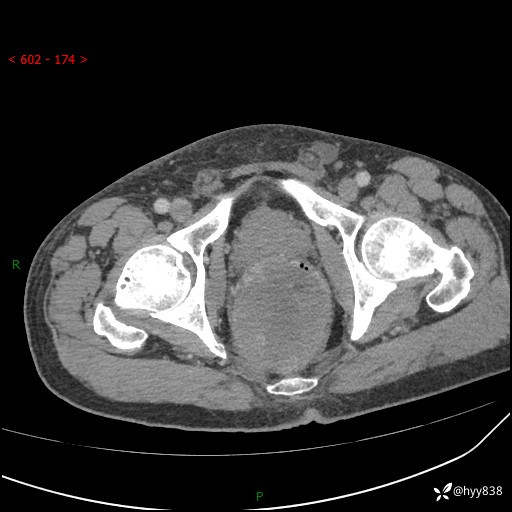

盆腔CT平扫+增强